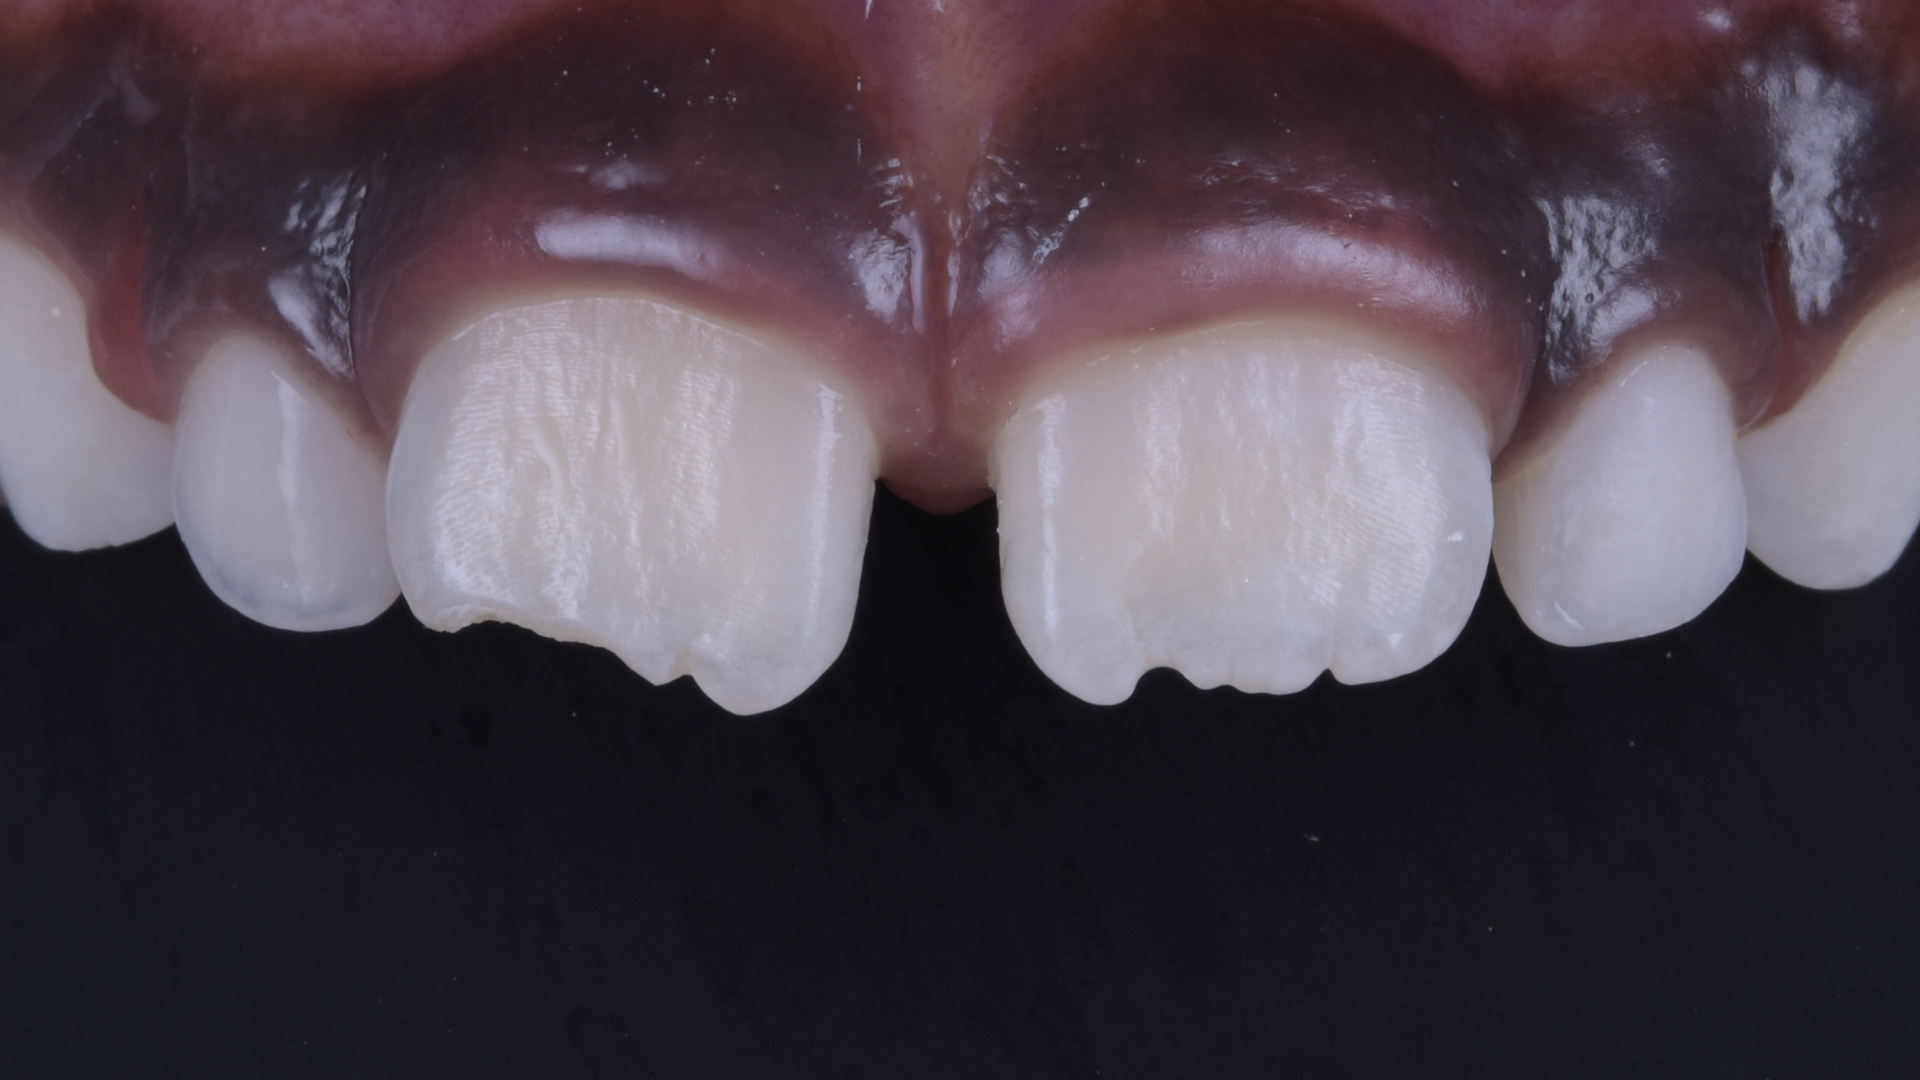

Ausgangssituation

Detailansicht der Oberkiefer-Frontzähne. Horizontale Kronenfraktur unter Einbeziehung der Inzisalkante sowie des distalen Anteils von Zahn 11.

Detailansicht des frakturierten Zahnes.

Ansicht von lateral.